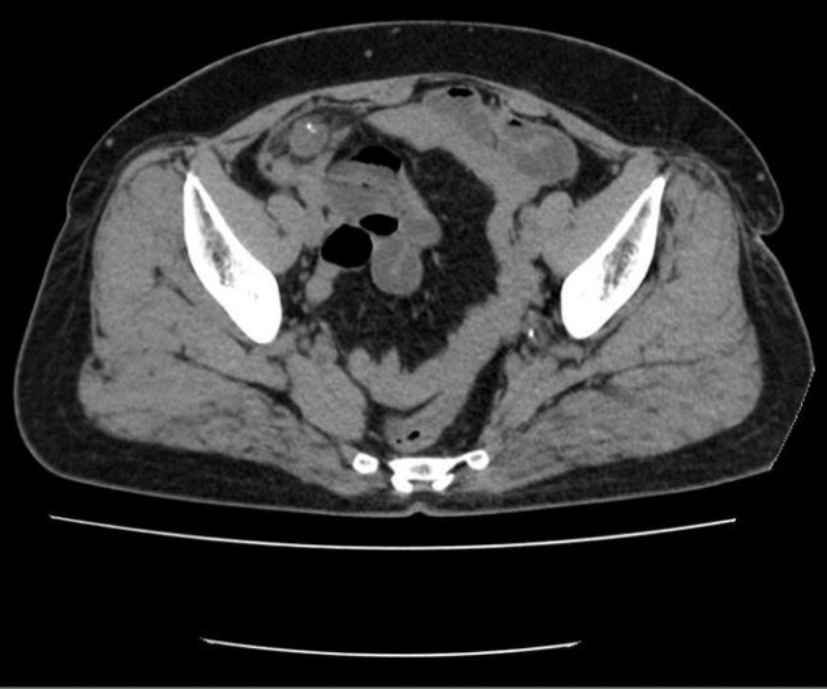

患者,女,56岁。2024年3月因“间断右下腹痛1月余”就医。患者1月余前无明显诱因开始出现右下腹痛,呈阵发性钝痛,无恶心、呕吐,无腹胀、腹泻,无畏寒、发热,无呕血、黑便,行B超示:右下腹阑尾区不均质低回声团,阑尾炎可能性大,给予对症抗感染治疗,症状有所缓解,但仍反复疼痛,为求进一步治疗收入当地医院。既往有高血压病史,16年前因肠套叠行结肠切除手术。查体:心肺检查未见明显异常,腹部平坦,无腹壁静脉曲张,腹部可见陈旧手术瘢痕,腹软,右下腹压痛,无反跳痛及肌紧张,腹部未触及明显肿块,叩诊呈清音,移动性浊音阴性,肠鸣音3次/分,未闻及血管杂音。入院后完善血常规:白细胞6.61*10^9/L (3.5~9.5)、消化系统肿瘤标记物:癌胚抗原2.4 ng/ml (13~150),甲胎蛋白3.87 ng/ml (≤7),类抗原19-9 31.9 ng/ml (≤34)均正常。腹部CT示:腹腔内部分小肠积液。右下腹局部见管状影,壁钙化。回盲部见多发微小结节,乙状结肠内见高密度灶(见图1(a)~(d))。肠镜示:回盲瓣呈唇状,阑尾肿大,开口处黏膜粗糙糜烂,蠕动可(见图2)。给予行腹腔镜下阑尾切除术,术中探查见:阑尾端侧与临近小肠致密黏连,无法分离,完整切除阑尾困难,为避免损伤黏连小肠,剪刀贴近黏连处将阑尾浆膜剪开,剥离阑尾,部分浆膜残留于小肠,距离阑尾根部0.5 cm结扎,切除阑尾。术后病理:送检破碎阑尾组织,部分管腔上皮呈高级别上皮内瘤变,少量破碎游离组织内见数个异型腺体浸润性生长,考虑癌变,高分化腺癌。组织碎,浸润层次不明确,阑尾肌层及浆膜层见多量无细胞黏液及炎症反应(见图3(a)图3(b))。患者术后5天顺利出院。

(a) (b)

Figure 3. Postoperative pathology of the appendix (HE×100)

3. 阑尾术后病理(HE×100)